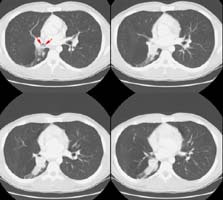

A CT scan of the chest was performed and revealed a heterogeneous soft tissue mass in the right interlobar bronchus with post-obstructive atelectasis.

A photo from the patient's bronchoscopy revealed the intralumenal mass. The mass proved to be a typical carcinoid or type I Kulchitsky cell carcinomas.